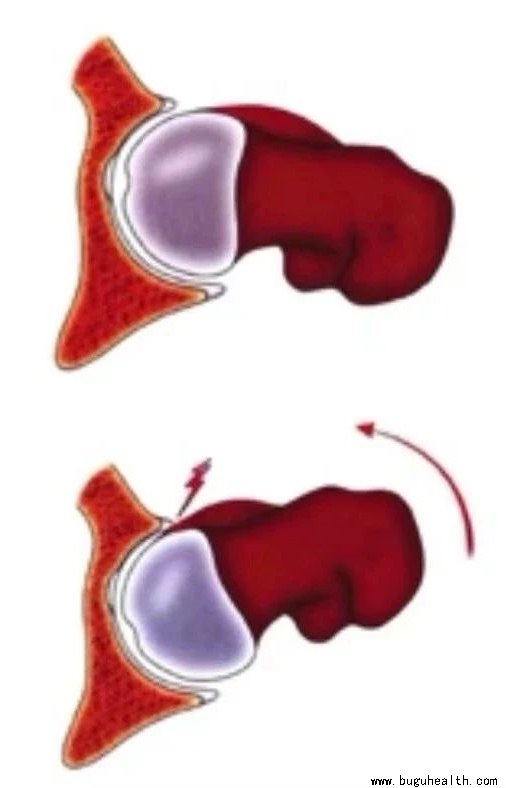

- ����ҽѧ���գ�ϥ�ؽڰ��°��������е���Ҫ�ԣ� BuGuRMC���ǿ���ҽ�����ģ���������ʦţҫ�� ��2023-01-31

- ϥϥ�ؽ�������������Ҫ�ij��عؽڣ�������վ�������к��˶�ʱ��ϥ�ؽھ�����������Ҫ�����á���ôϥ�ؽ�������ܹ��е�����������أ���͵�˵��ϥ�ؽ���һ����Ҫ����֯�������°塣����˼�壬���°�����Ӿ������£����Ը��ɹ���������ܺõ����ϣ�������ƽ�棬�������ֹ�ƽ̨�ϡ���һ��������Ϊ�ڲ���°��������.....